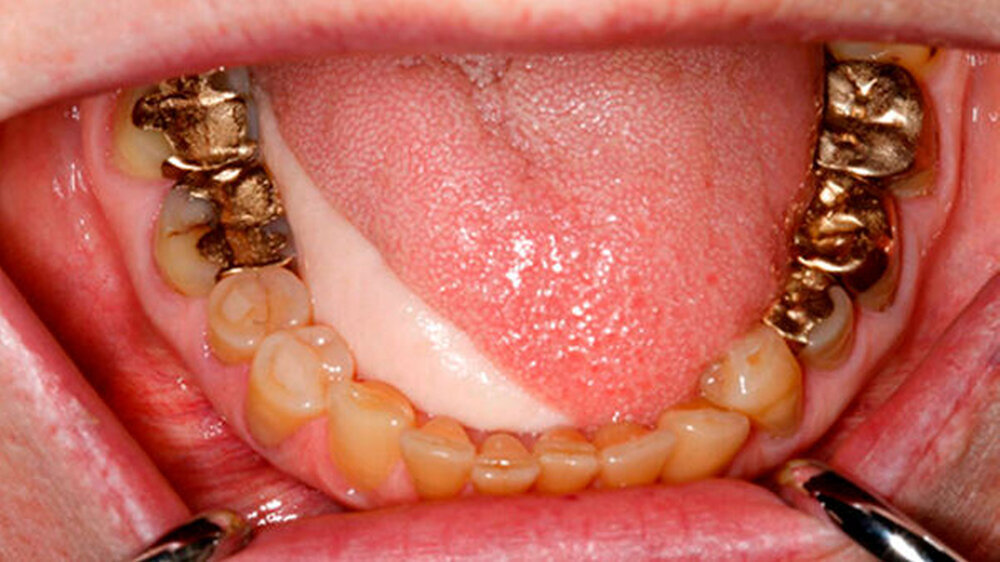

Kurze Zeit später wurde der Tumor im Bereich der Zungenunterseite und des Zungenrandes in toto entfernt. Das dadurch entstandene Volumendefizit stellten die Hamburger MKG-Spezialisten mit einem Transplantat vom Unterarm wieder her.

Damit das Transplantat anwächst, muss die Blutversorgung während der Einheilungsphase sichergestellt sein. Der Anschluss an den Blutkreislauf, konkret an die großen Halsgefäße, wurde in mikrochirurgischer Feinarbeit unter Verwendung eines hochauflösenden Operationsmikroskops erfolgreich durchgeführt.